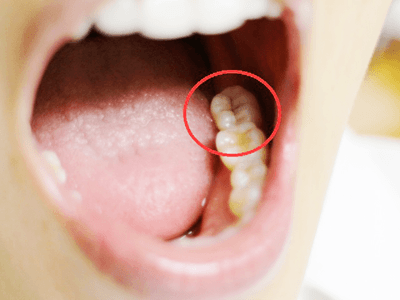

口腔内カメラです。

実際には自分の目で直接見ることができない口の中を、拡大してみることができます。

なんと、歯に穴が開いてしまっているのが分かります!

この穴を治すために使う道具を説明して、いざ治療をしていきますが、